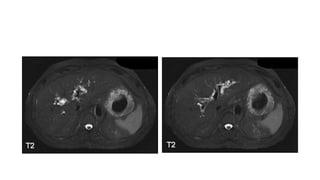

Caso Cerrado 21

Abril Ana Casas

Historia • Varón de 50

años con historia de hepatitis crónica e hipertensión portal